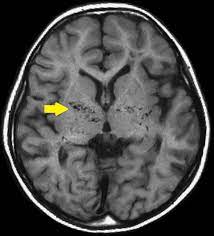

- MRI(Magnetic Resonance Imaging): MRI를 사용하여 뇌혈관을 자세하게 평가하고 혈류 문제를 확인할 수 있습니다.

- 혈관조영술(Cerebral Angiography): 혈관조영술은 혈관 내부 구조를 자세하게 시각화하기 위해 사용됩니다. 이 절차는 모야모야병을 진단하는 가장 확실한 방법 중 하나입니다.